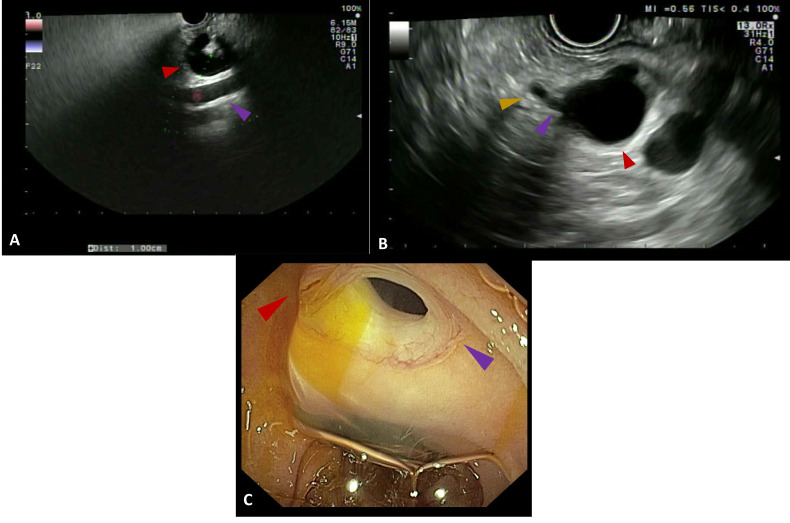

近年来,偶发性胰腺囊性病变(PCLs)的发病率有所上升,这主要是由于成像技术的进步和使用的增加。内镜超声(EUS)已成为评估和表征pcl的重要工具,可以进行详细的形态学评估,并有助于识别进展为高级别不典型增生或浸润性胰腺癌的高风险病变。本综述旨在概述EUS在pcl评估中的关键方面,涵盖了从形态学评估和对比度增强成像到弹性成像,细针穿刺生物标志物分析,细胞学,DNA测序,组织学评估以及共聚焦激光内镜或人工智能的新兴作用的一系列模式。此外,我们还讨论了pcl的EUS治疗方式,目前EUS的局限性,预期的技术进步以及领先科学学会推荐的pcl临床处理的多种管理策略。

The incidence of incidental pancreatic cystic lesions (PCLs) has risen in recent years, largely due to advances in and increased use of imaging techniques. Endoscopic ultrasound (EUS) has become a crucial tool for evaluating and characterising PCLs, allowing for detailed morphological assessment and aiding in the identification of lesions with a higher risk of progression to high-grade dysplasia or invasive pancreatic carcinoma. This review aims to outline the key aspects of EUS in the evaluation of PCLs, covering a range of modalities from morphological assessment and contrast-enhanced imaging to elastography, fine-needle aspiration for biomarker analysis, cytology, DNA sequencing, histological evaluation and the emerging role of confocal laser endomicroscopy or artificial intelligence. Additionally, we address therapeutic EUS modalities for PCLs, the current limitations of EUS, anticipated technological advancements and the diverse management strategies recommended by leading scientific societies for the clinical handling of PCLs.